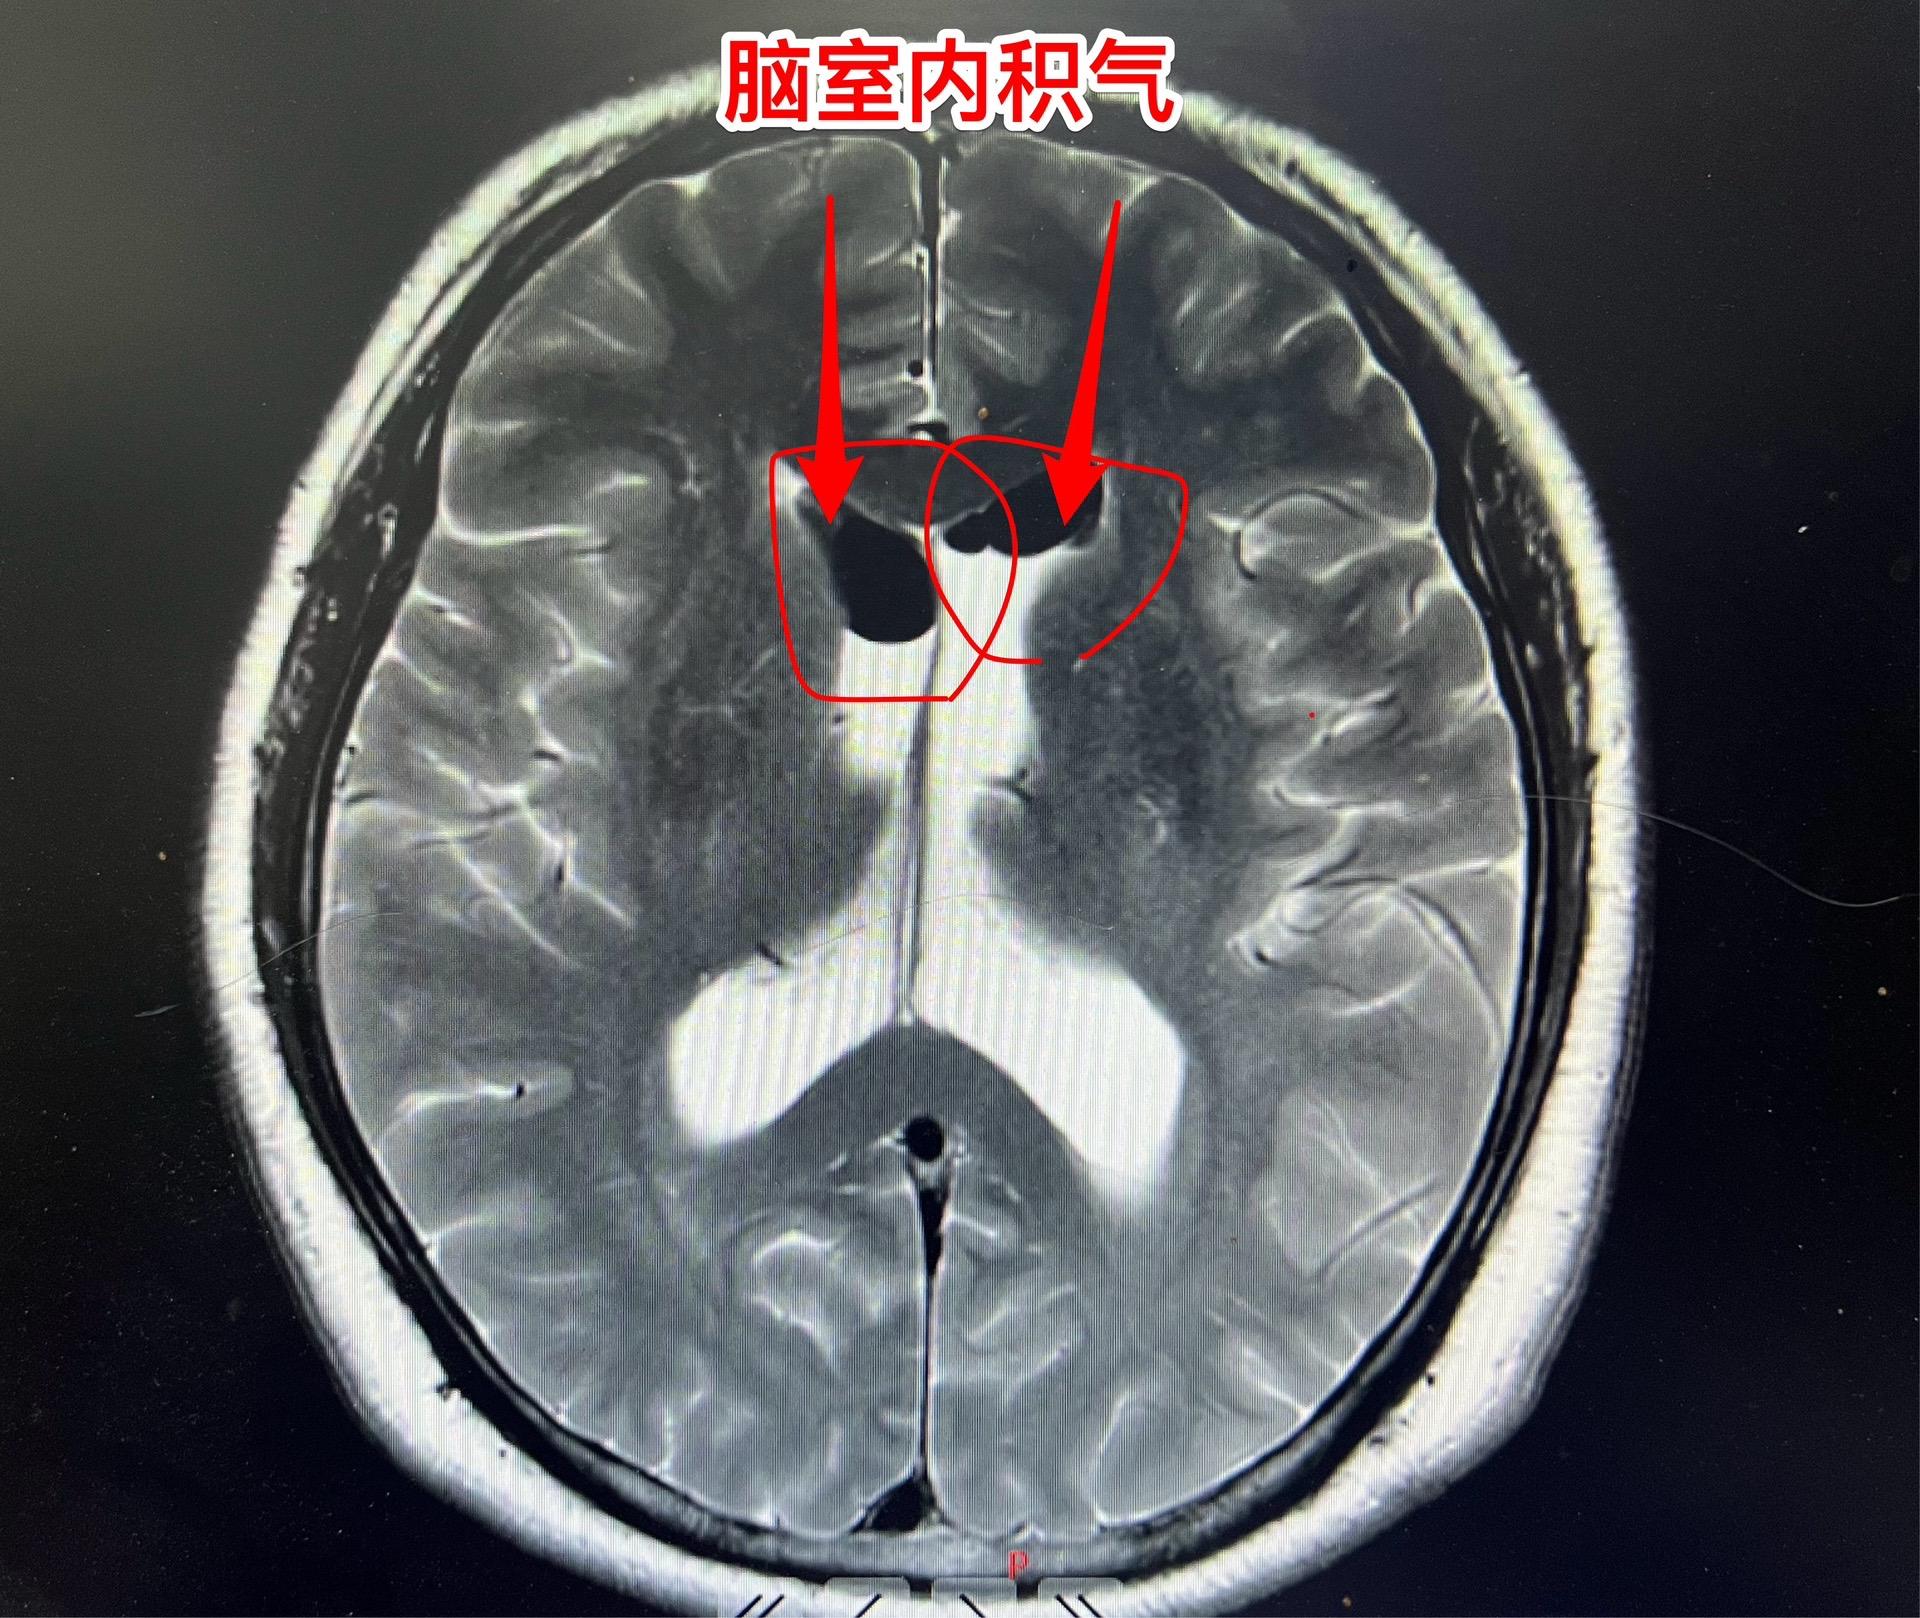

吃药能让垂体瘤消失?这不是传说。垂体瘤中有一种特殊的瘤叫泌乳素瘤,可以通过吃药就化掉了!这不是传说!最常用的药叫溴隐亭! 但是,切记:如果停药了,肿瘤又会长出来的! 这个51岁的承德市男性,3年前因视力下降到医院检查发现了垂体瘤,经过化验泌乳素,被确诊为泌乳素瘤。口服溴隐亭这个神药,肿瘤变小了,吃药两年后病人因为头晕、行走困难而停药。停药一年后肿瘤又复发了,肿瘤体积很大,侵蚀了垂体窝骨质进入蝶窦内! 2024年10月25日在我科复查泌乳素,显示泌乳素水平远远